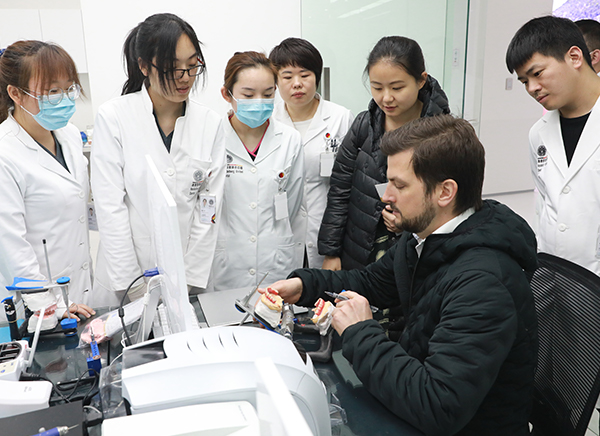

中德口腔专家,您的专属牙医

每一年,我们都要面对近万名缺牙患者

深知每个人因生活习惯、经历和身体情况各异

形成了不同的牙齿困扰

为此,我们特别集结国内外口腔领域优秀的医资力量

以丰富的医学经验为智慧核心,

以万则成功案例为临床参考

确保您能得到最适宜自己的种植牙治疗方案

坚守学术至上 ,推行教研合一

建院至今,

海德堡联合口腔共举办了

数十场国内外学术会、交流会、分享会、培训会

十余国、超百位学者参与其中

这个数字还在持续增加……

重视学术研究,人才培养,

为提高口腔医疗质量

更为患者提供优质严谨的诊疗服务